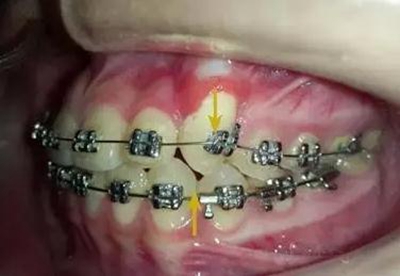

牽引了三四個(gè)月尖牙終于長(zhǎng)出來了,也遠(yuǎn)離了側(cè)切牙

當(dāng)尖牙到達(dá)了指定位置后,又采用了主弓絲和附弓絲,主弓絲采用了不銹鋼絲方絲,有效的避免了反作用力引起相鄰的牙齒出現(xiàn)小開合, 維護(hù)牙弓形態(tài)。

主弓絲和輔弓絲的結(jié)合使用,可以有效避免出現(xiàn)小開合,同志們一定要注意啊!

一個(gè)月后尖牙下來很多,

加上垂直牽引,尖牙下來的更快了